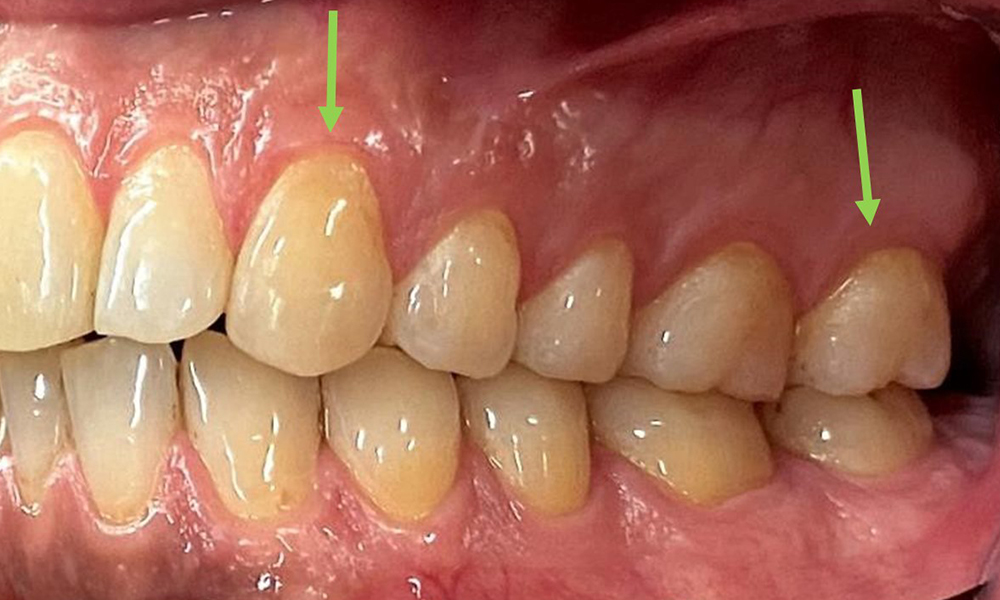

There were no pathological extraoral findings. During intraoral examination, inspection of the frontal view revealed brownish discolouration near the keratinised gingiva and at the transition to the moveable mucosa (Fig. 2), which could be attributed to nicotine consumption. Whitish mucosal lesions were observed on the palate, particularly near the maxillary molar palatal surfaces, indicating increased keratinisation and can also be attributed to nicotine consumption. The tongue was covered with a removable white and brownish coating.

At 1 to 3 mm, the clinical probing depths were within the physiological range. Maxillary recessions of up to 1 mm were observed from 13 to 16 and 23 to 27. The BOP was 15%.

Close-up view of teeth

Fig. 5: Close-up view of teeth 45 to 47. The green arrows show dental attrition and erosions of the buccal cusps with partial enamel loss, © Dr R. Krapf

The arrows indicate plaque accumulations in the cervical region

Fig. 8: The arrows indicate plaque accumulations in the cervical region, © Dr R. Krapf